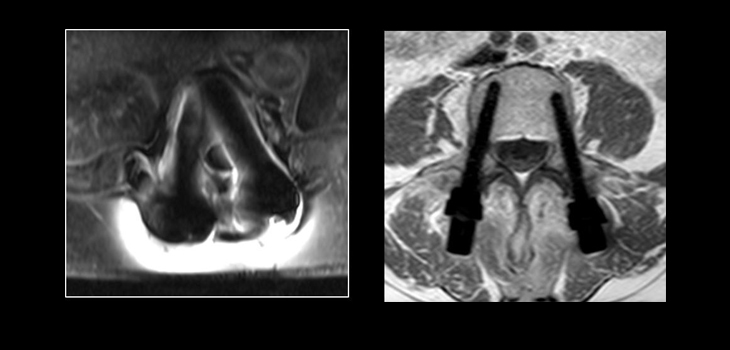

The implants are made of carbon fiber-reinforced polyetheretherketone (CFR-PEEK). The threaded portion of the pedicle screws is encased within a thin titanium shell.

“Among those advantages are: no backscattering during radiotherapy (including particle therapy), which allows the use of radiation therapy without harming the healthy surrounding tissue; minimal attenuation of External Beam Radiation (EBRT), allowing radiation to pass through the implant with almost zero reduction in the radiation dose level; and no artifact in CT, for optimal radiation CT planning.”

In addition, the company says the implants offer “superior fatigue strength, beneficial for a patient population known for extended delays in healing. Additionally, the CarboFix implants offer enhanced follow-up abilities due to minimal artifacts during CT/MRI scans, facilitating early detection of possible tumor recurrence.”